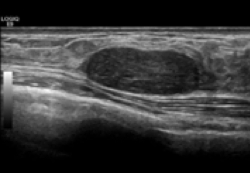

高周波探触子と画像処理技術の向上により、軟部組織から整形領域における関節腔内観察などにも超音波が活用されています。

乳腺・甲状腺の画像診断といえば超音波となったように、リウマチの画像診断も超音波がファーストチョイスになる日がくる事を期待しつつ、我々も研鑽を怠りません。